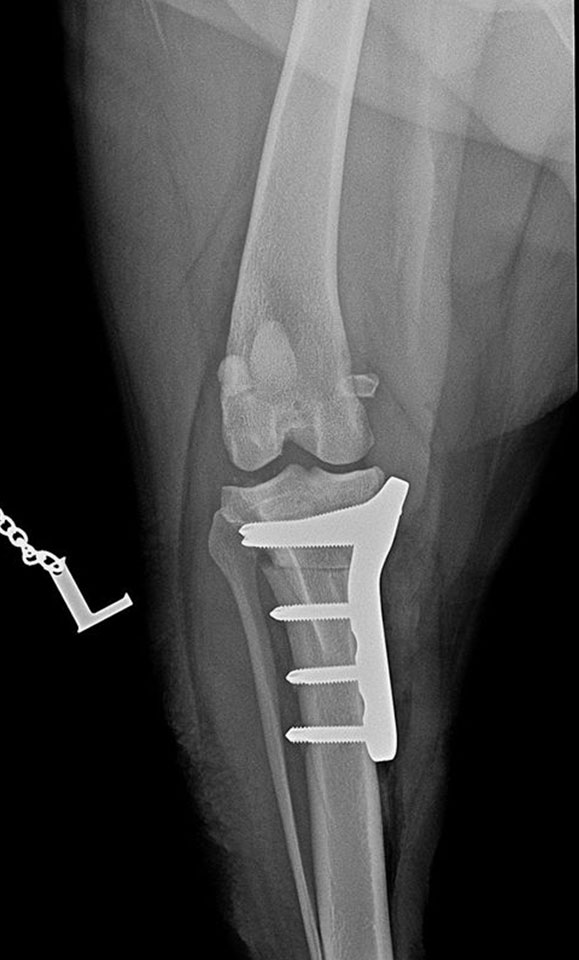

Shar-pei, cruciate ligament rupture surgery, TPLO with small pre-contoured polyaxial plate.

Sawed with R21 blade. Temporary fixation with 1,4 mm K-wire through the plate’s micro hole, which helps untill the locking poliax screws are driven in.